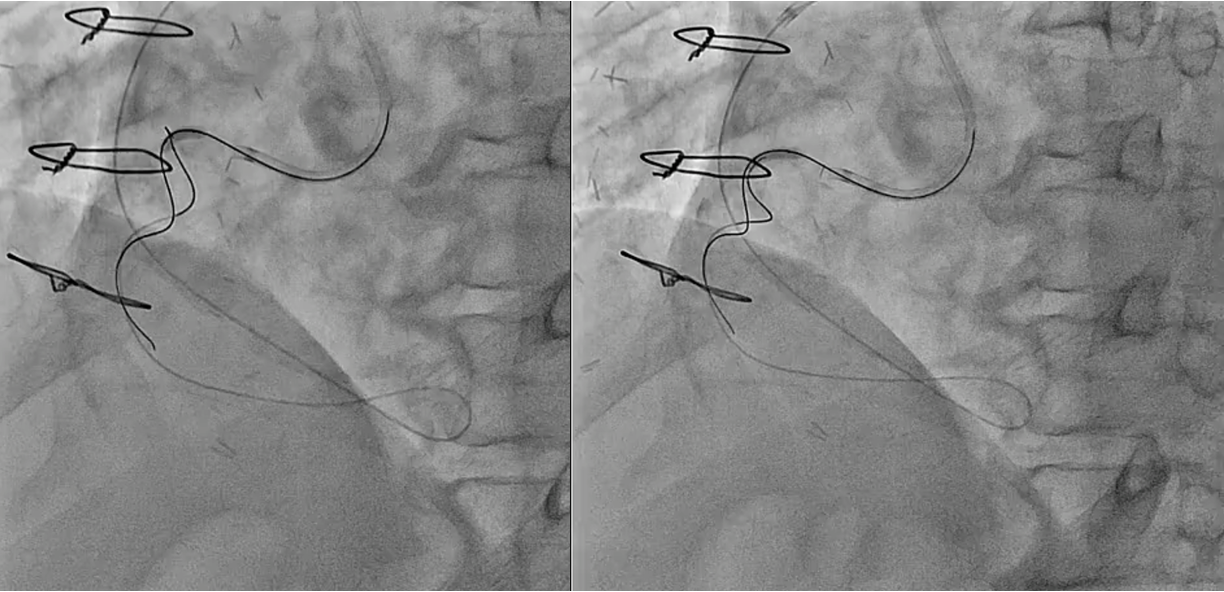

PCI for the degenerated SVG was determined to be at high risk of distal embolism so we planned to perform PCI for native RCA. Antegrade wire crossing was thought to be difficult (J-CTO score was 3 : calcification, bending and lesion length), therefore we planned retrograde approach via SVG. To avoid ischemia during the retrograde procedure, we dilated the severe stenotic lesion in SVG with small balloon and then micro catheter was advanced. It was very difficult to pass the graft anastomosis, but reverse wire technique at distal RCA was effective. Even after the advancement of both antegrade and retrograde wires, it was also difficult to pass the CTO lesion due to strong bending. Finally, retrograde wire was passed with Reverse CART technique and externalization was achieved. After DES implantation, native RCA was nicely revascularized.